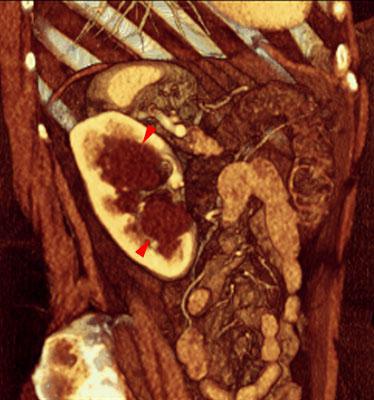

Quiste renal pielosinusal